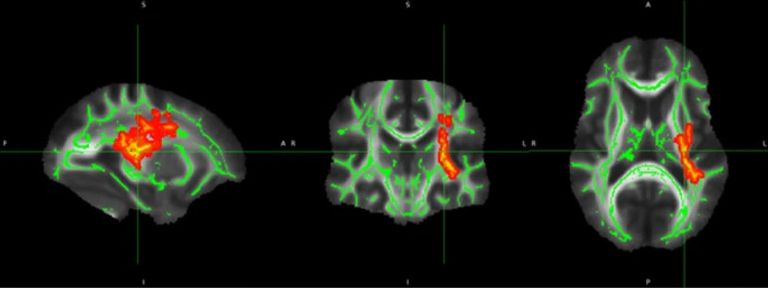

Although some studies have shown neuroimaging and neuropsychological alterations in post-COVID-19 patients, fewer combined neuroimaging and neuropsychology evaluations of individuals who presented a mild acute infection. Here we investigated cognitive dysfunction and brain changes in a group of mildly infected individuals. We conducted a cross-sectional study of 97 consecutive subjects (median age of 41 years) without current or history of psychiatric symptoms (including anxiety and depression) after a mild infection, with a median of 79 days (and mean of 97 days) after diagnosis of COVID-19. We performed semi-structured interviews, neurological examinations, 3T-MRI scans, and neuropsychological assessments. For MRI analyses, we included a group of non-infected 77 controls. The MRI study included white matter (WM) investigation with diffusion tensor images (DTI) and functional connectivity with resting-state functional MRI (RS-fMRI). The patients reported memory loss (36%), fatigue (31%) and headache (29%). The quantitative analyses confirmed symptoms of fatigue (83% of participants), excessive somnolence (35%), impaired phonemic verbal fluency (21%), impaired verbal categorical fluency (13%) and impaired logical memory immediate recall (16%). The WM analyses with DTI revealed higher axial diffusivity values in post-infected patients compared to controls. Compared to controls, there were no significant differences in the functional connectivity of the posterior cingulum cortex. There were no significant correlations between neuropsychological scores and neuroimaging features (including DTI and RS-fMRI). Our results suggest persistent cognitive impairment and subtle white matter abnormalities in individuals mildly infected without anxiety or depression symptoms. The longitudinal analyses will clarify whether these alterations are temporary or permanent.